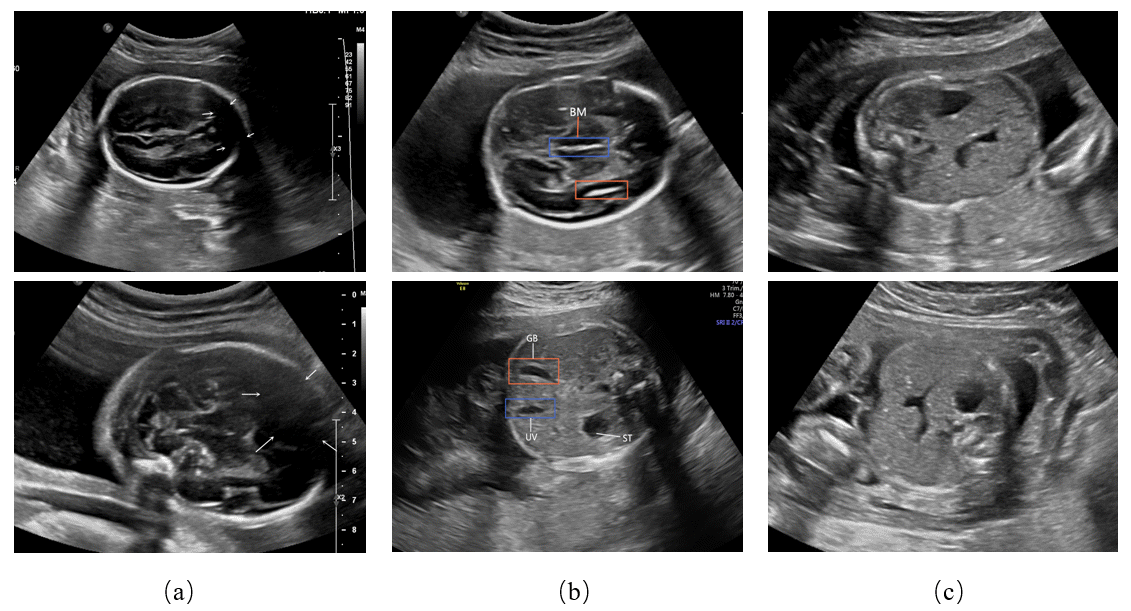

Fig. 7, Fig. 8 and Fig. 9 depict the comparison of our results with the manually labeled images by experts in the head section, abdominal section, and heart section, respectively. Our method displays the classification and detection results simultaneously to assist in sonographers’ observation. It can be seen that our method is perfectly aligned with professional sonographers.